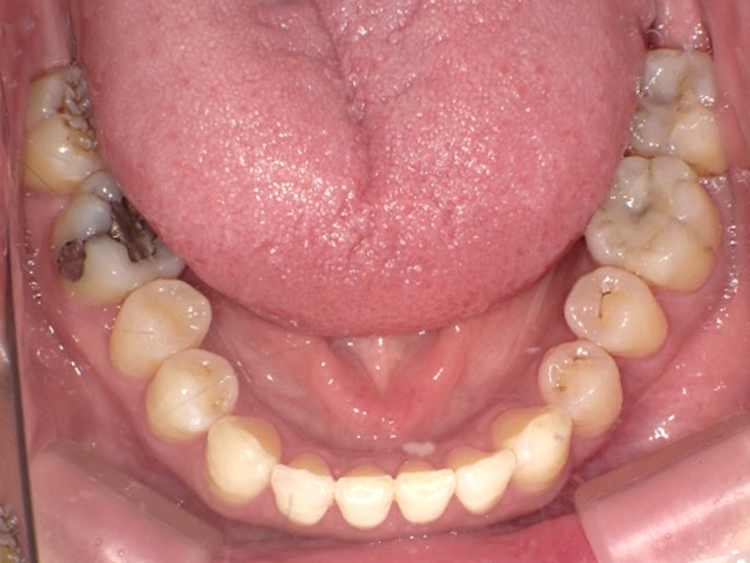

症例6

Before

After

| 主訴 | 噛み合わせが気になる |

|---|---|

| 年齢 | --- |

| 治療 期間 |

約2年11ヶ月 |

| 治療 内容 |

インビザラインコンプリヘンシブ 右上6番・左上6番ALLセラミッククラウン |

| 治療費 | ¥1,116,000(税込)/調整料含む |

| 治療のリスク | 歯を動かすことで、歯茎が下がるリスクある。 矯正終了後は、リテーナーを使用し、後戻りを防ぐ必要がある。 |